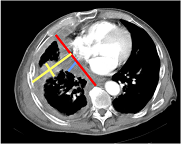

Volumetry of Mesothelioma

Uni-/Bi-dimensional measurement of mesothelioma

Volumetric measurement of mesothelioma

Liu F, Zhao B, Krug LM, …, Schwartz LH. Assessment of Therapy Responses and Prediction of Survival in Malignant Pleural Mesothelioma through Computer-Aided Volumetric Measurement on CT Scans. J Thorac Oncol. 2010 Jun; 5(6):879-84.